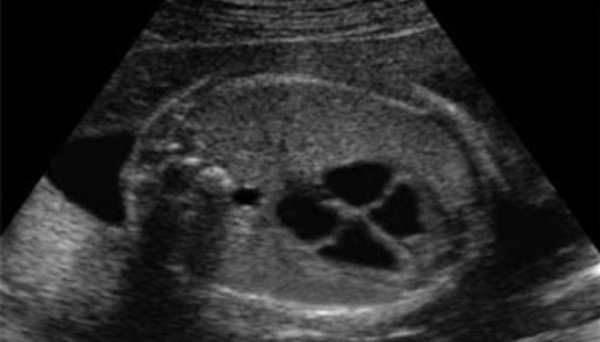

Ultrasound Elastography is a non-invasive imaging technique that measures the stiffness or elasticity of tissues in the body. It is commonly used to assess the liver, thyroid, breast, and other soft tissues for signs of disease, particularly fibrosis or cancer.

By detecting changes in tissue stiffness, elastography provides valuable diagnostic information that complements traditional ultrasound, allowing for earlier detection of diseases such as liver cirrhosis or cancerous tumors.